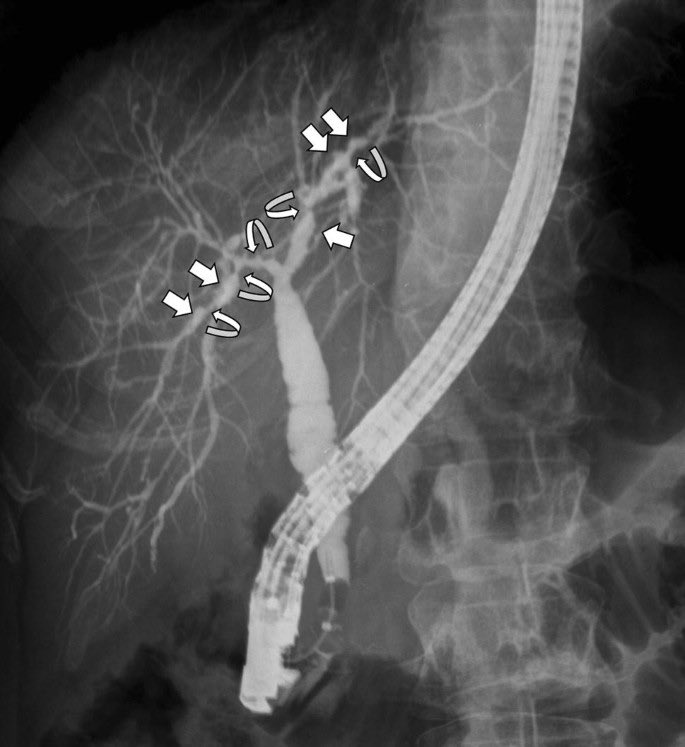

📍primary sclerosing cholangitis (beads on string sign)